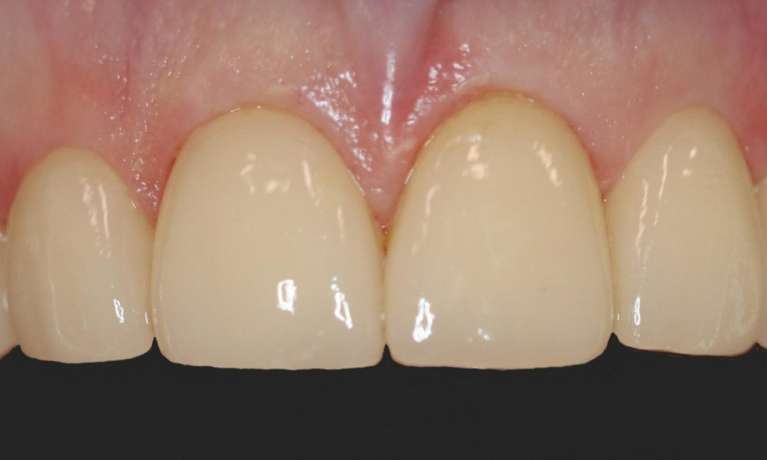

Stunning smile transformation with composite bonding on the four upper front teeth completed with a professional whitening treatment for a radiant and natural look.